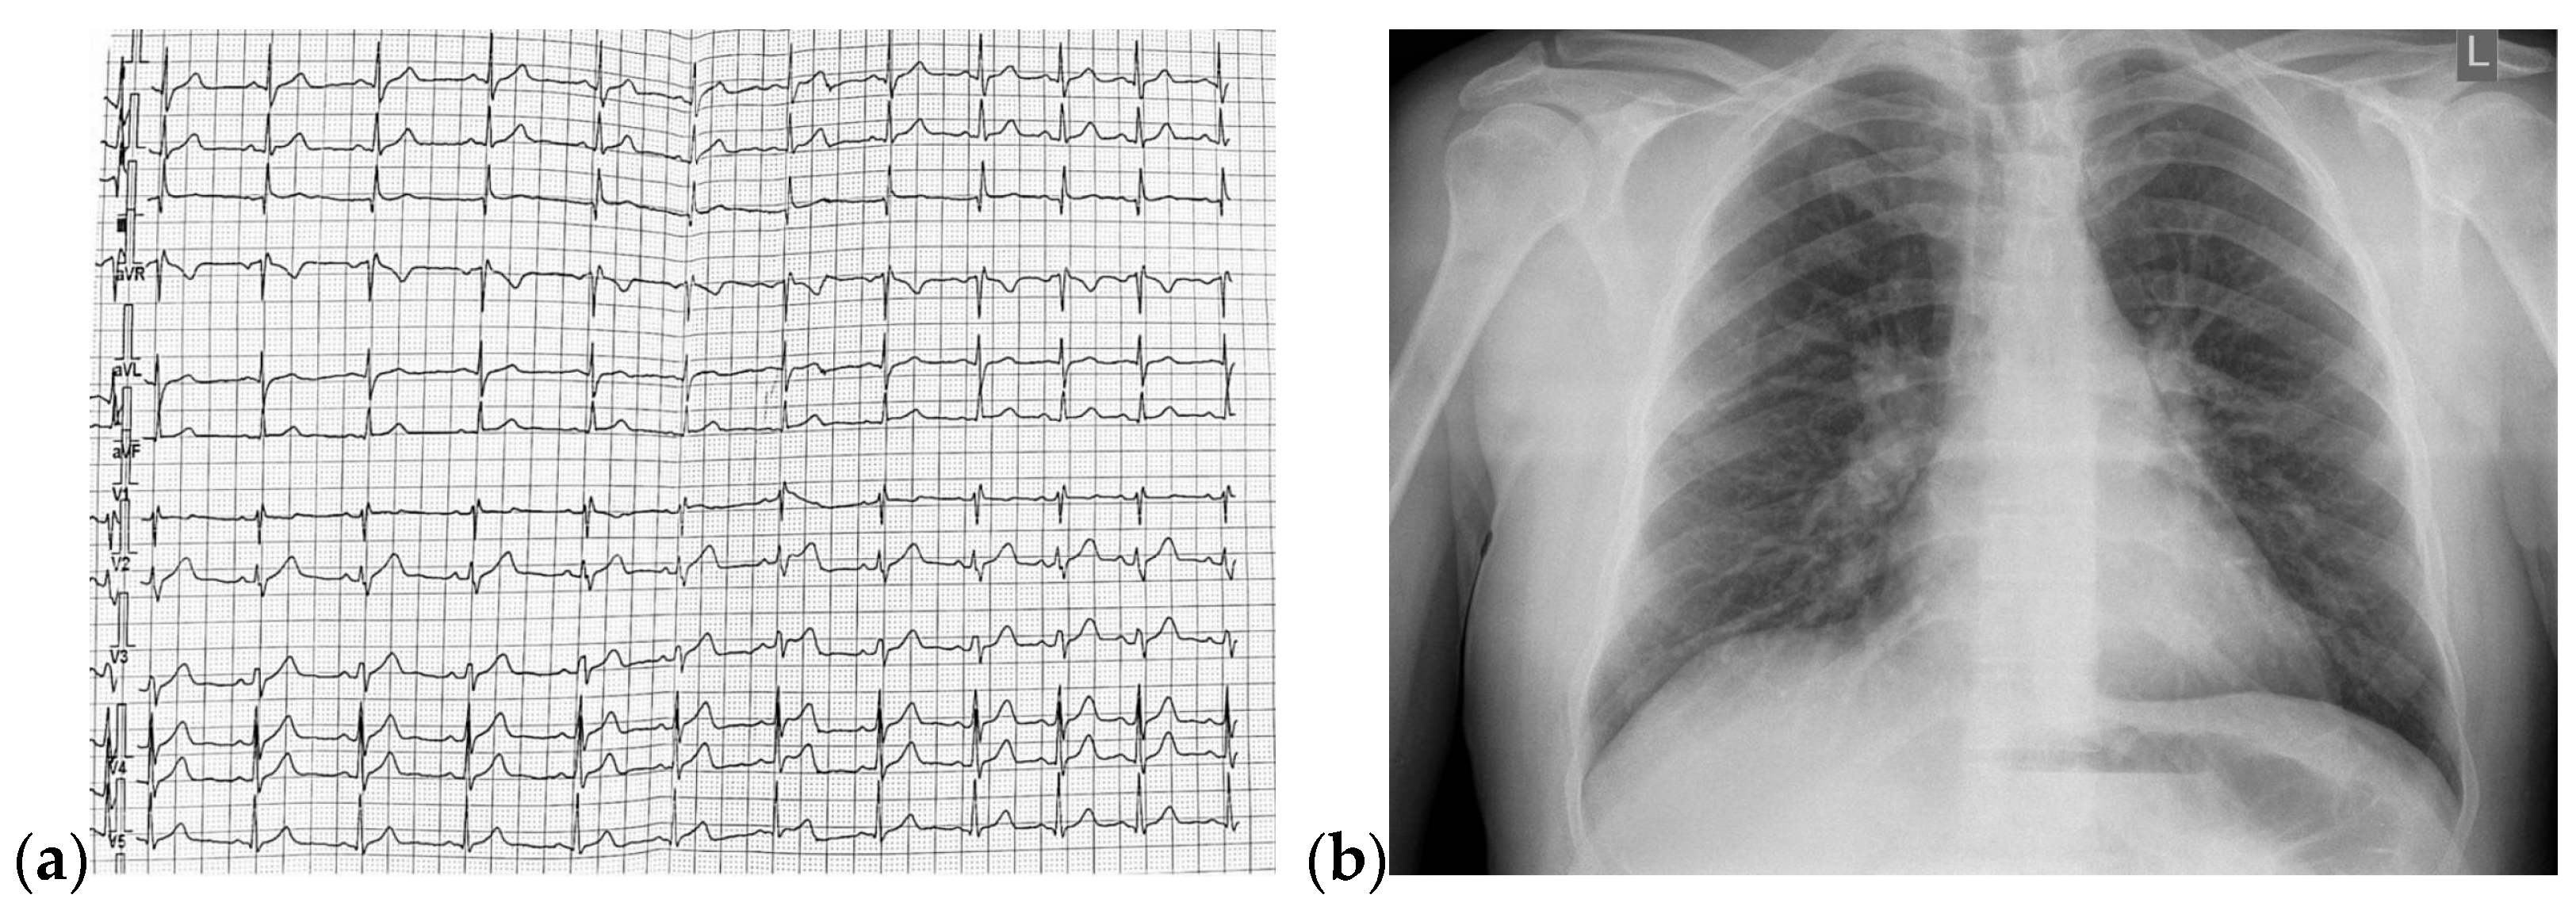

The TTE performed on admission showed a non-dilated left ventricle with an ejection fraction (EF) of 51% (using Simpson’s method), dilated right chambers, mild functional tricuspid regurgitation, mild pulmonary hypertension, tricuspid annular plane systolic excursion of 19 mm, inferior vena cava (IVC) with 18 mm diameter, and respiratory variability greater than 50%. The TTE raised the suspicion of ASD with significant hemodynamic shunt (Qp/Qs = 2.24) (Figure 2 and Figure 3).

Figure 2.

TTE on admission: (a) Parasternal long axis view with enlarged diameter of RV; (b) Apical 4-chamber view, tricuspid continuous wave Doppler flow, with a maximum RV-RA gradient of 32.33 mmHg; (c) Apical 4-chamber view, EF = 51% (Simpson’s method); Abbreviations: TTE—transthoracic echocardiography; RV—right ventricle; RA—right atrium; EF—ejection fraction.

Figure 3.

TTE on admission: (a) Parasternal long axis view measuring LVOT diameter = 2 cm; (b) Parasternal short axis view: Pulmonic VTI = 20.3 cm; (c) Parasternal short axis view: pulmonary artery trunk = 2.2 cm; (d) Apical 5 chamber view: Systemic VTI = 17.6 cm, Qp/Qs = 2.24; Abbreviations: TTE—transthoracic echocardiography; LVOT—left ventricle outflow tract; VTI—velocity-time integral.